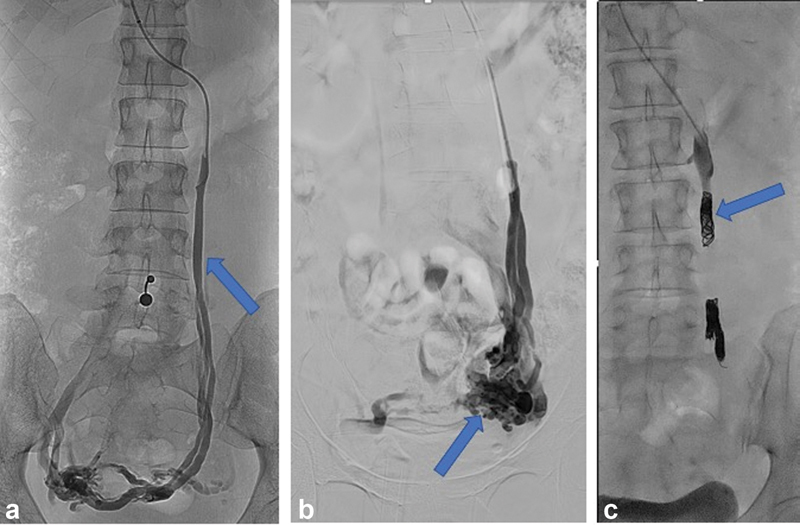

There is little consensus regarding how many of the main pelvic veins should be treated in one session, and/or in total. Some authors propose a limited, stepwise approach by first treating the left or bilateral OVs. 49 56 57 Other authors recommend complete treatment of all four main pelvic veins, namely, the left ovarian vein (LOV), right ovarian vein (ROV), left internal iliac vein (LIIV), and right internal iliac vein (RIIV) and may advocate including closure of communicating veins to the lower limb or gluteal veins. 14 51 52 55 58 59 Although publications exist describing coil embolization of the IIV, caution should be made prior to placement of coils in this component of the pelvic venous anatomy due to concerns of coil migration from this specific location. Fig. 3 shows an example of left OV embolization.

Fig. 3.

Fluoroscopic images demonstrate ( a ) left ovarian venography showing retrograde flow in the left ovarian vein (arrow) and filling of periovarian varices. ( b ) Balloon occlusion venography of the left ovarian vein shows left periovarian varices (arrow). ( c ) Fluoroscopic image showing occlusive coils in the left ovarian vein (arrow).